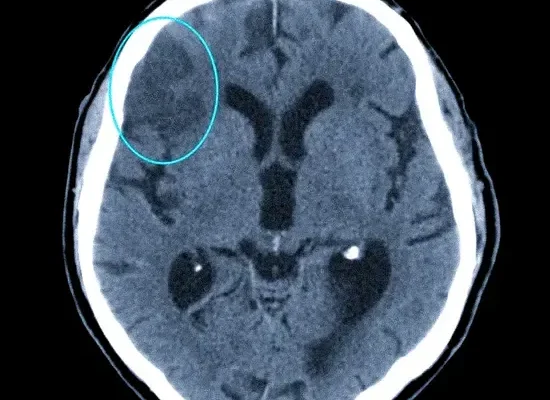

Искусственный Интеллект и МРТ: Как Мы Научили Машину Видеть Больше, Чем Глаз В мире, где технологии развиваются с невероятной скоростью, мы, как энтузиасты